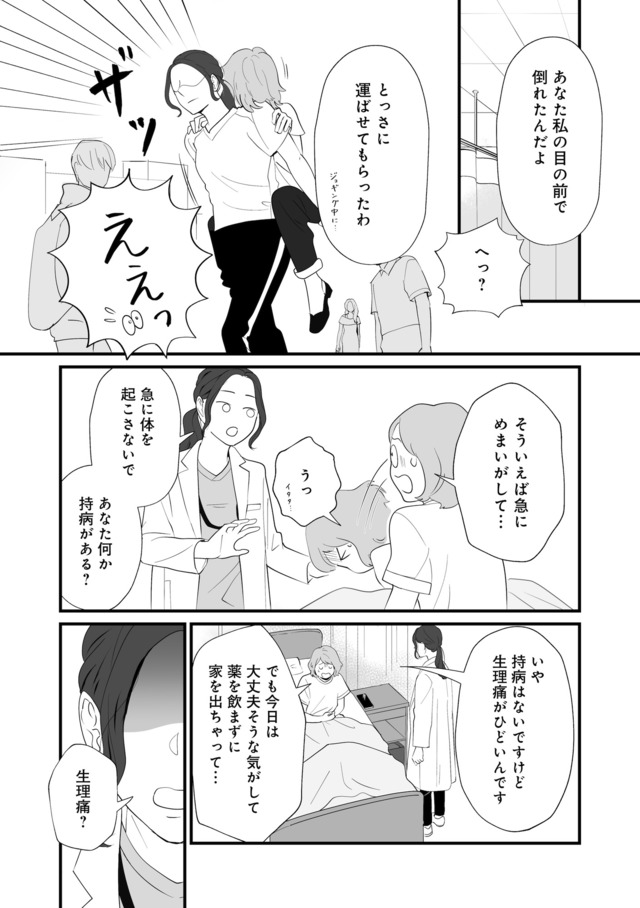

生理痛やPMSに苦しむあかり。通勤中、貧血で倒れて病院に運ばれたことをきっかけに、自分にあった生理用品や治療法を教えてもらうことに。

※本記事は、漫画・くゑ 、監修・高橋 怜奈 の書籍『産婦人科医に聞く わたしとカラダの選択肢』から一部抜粋・編集しました。